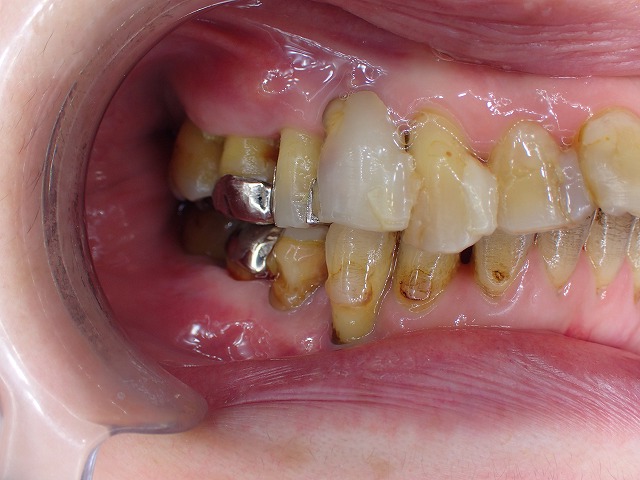

右側の様子

重度歯周病の人は、虫歯も多く

レジン充填などが多いため、

充填を連結することで、固定しています。